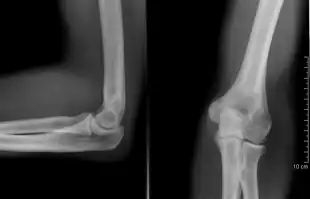

The elbow undergoes dynamic development of ossification centers through infancy and adolescence, with the order of both the appearance and fusion of the apophyseal growth centers being crucial in assessment of the pediatric elbow on radiograph, in order to distinguish a traumatic fracture or apophyseal separation from normal development. The order of appearance can be understood by the mnemonic CRITOE, referring to the capitellum, radial head, internal epicondyle, trochlea, olecranon, and external epicondyle at ages 1, 3, 5, 7, 9 and 11 years. These apophyseal centers then fuse during adolescence, with the internal epicondyle and olecranon fusing last. The ages of fusion are more variable than ossification, but normally occur at 13, 15, 17, 13, 16 and 13 years, respectively.[16] In addition, the presence of a joint effusion can be inferenced by the presence of the fat pad sign, a structure that is normally physiologically present, but pathologic when elevated by fluid, and always pathologic when posterior.[17]

Right: AP X ray of a dislocated right elbow

Fractures

There are three bones at the elbow joint, and any combination of these bones may be involved in a fracture of the elbow. Patients who are able to fully extend their arm at the elbow are unlikely to have a fracture (98% certainty) and an X-ray is not required as long as an olecranon fracture is ruled out.[23] Acute fractures may not be easily visible on X-ray.